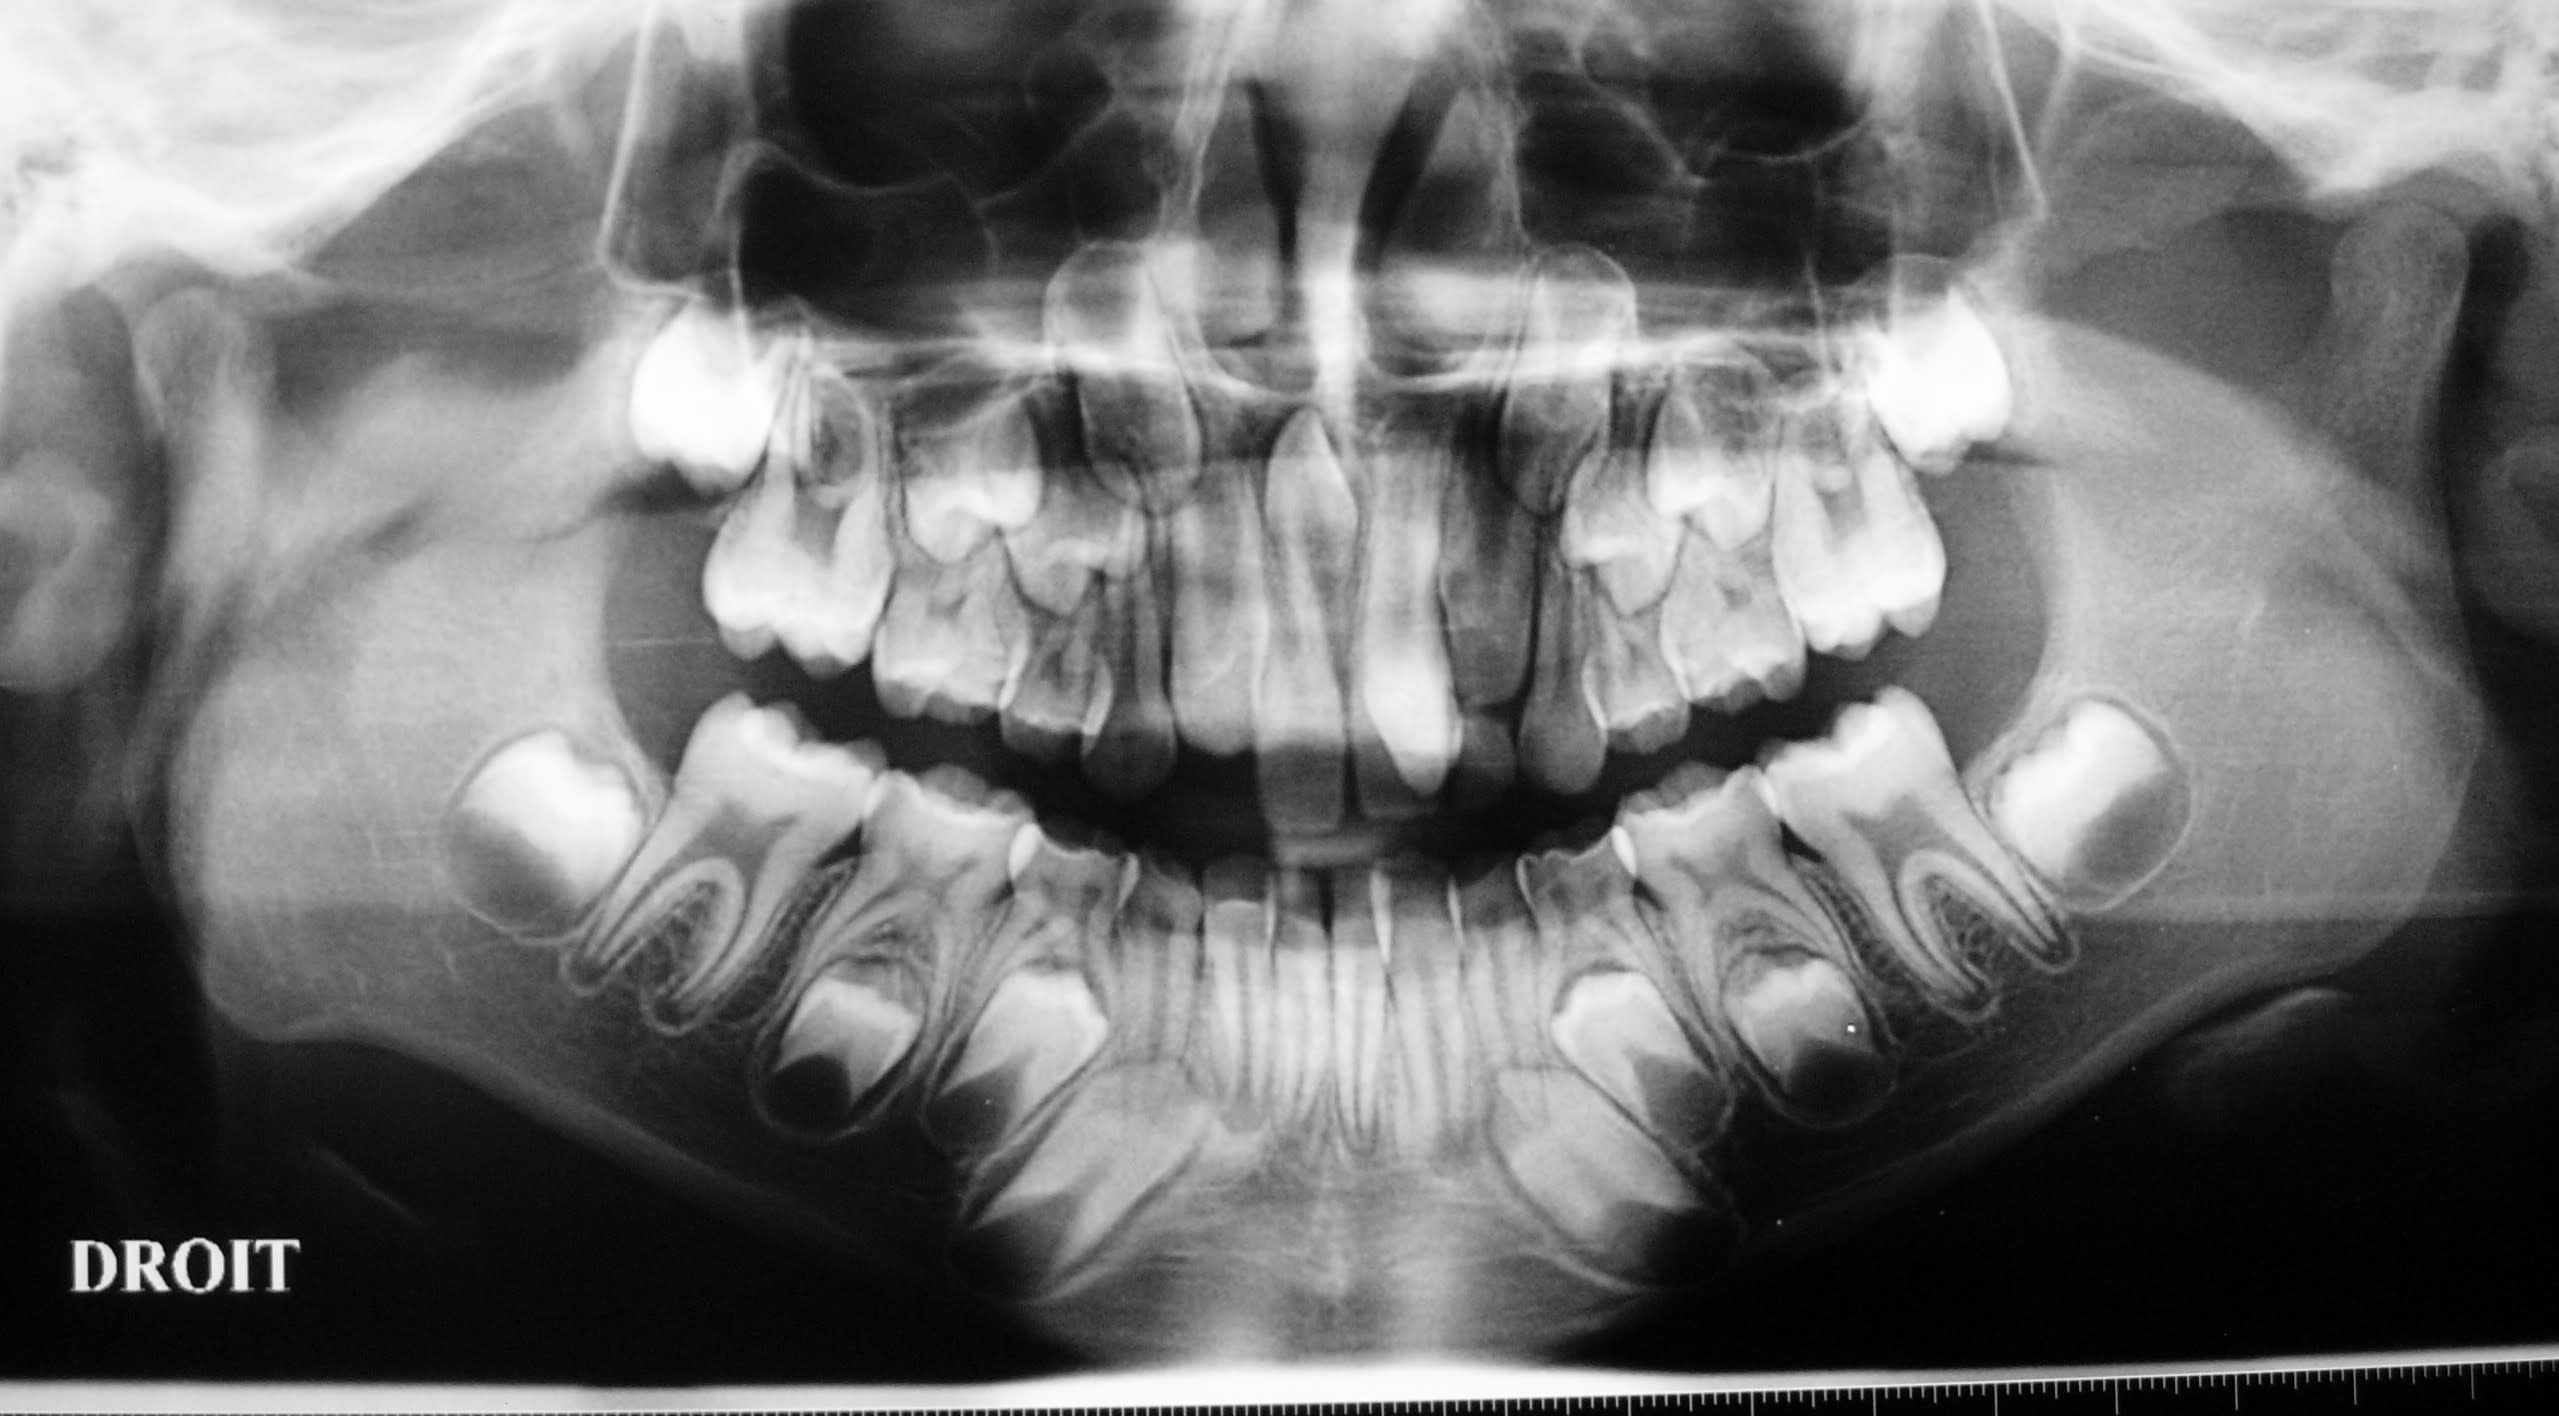

Allez, je lance le sujet, envoyez vos photos ou vidéo.

J'ai pu garder le paquet vasculo nerveux palatin antérieur. Les grincheux diront que çà sert à rien, mais j'avais le temps et je trouve çà classe :))

(le trou en palatin de la 21 c'était un odontoïde évolué en bouche que l'on ne voit pas bien sur les clichés)

- superbes tes reconstructions 3D.

Les reconstructions sont faites avec le logiciel gratuit Osirix (uniquement disponible sous MAC) à partir du CD du dentascan fourni par le radiologue.